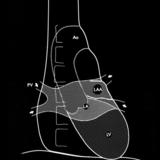

Left chambers PA